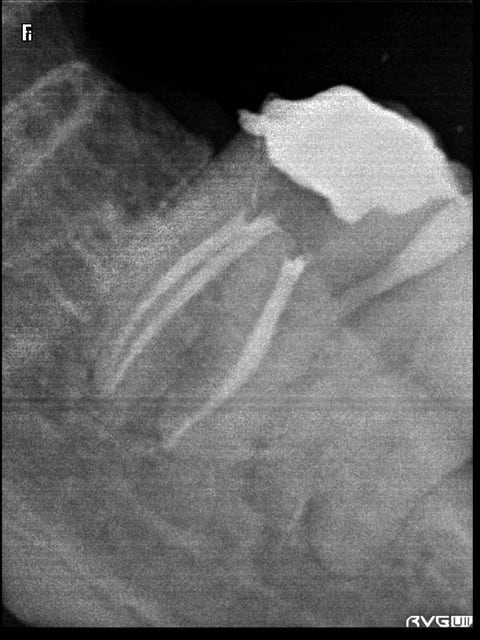

(Des fois l'endo ça marche. Protaper + Gutta condensor)

Reste plus qu'à faire la même sur tous mes cas...

R5 ngbr3g - Eugenol